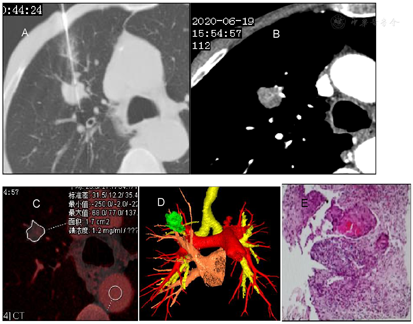

男性,70岁,咳嗽、咳痰1个月余,图ACT平扫右肺上叶前段可见1.5cm×1.7cm×2.9cm结节,边缘可见浅分叶征,上叶支气管开口处可见杯口征,平扫CT值43HU。增强扫描动脉期病灶实质部分强化,CT值62HU。静脉期65HU,延迟期68HU。图B示肿瘤内可见肿瘤微血管CT成像征。通过碘图分析及癌灶碘参数测量:动脉期IC:1.1mg/ml,NIC;0.08。图C示静脉期IC1.2mg/ml,NIC:0.26,延迟期IC0.9 mg/ml NIC0.31。静脉期碘图(0.34)诊断肺癌(腺癌)的阈值。纵膈隆突前、隆突下增大淋巴结碘图AEF值0.64~0.74,考虑淋巴结转移瘤,隆突左侧淋巴结0.58,考虑非转移性淋巴结。VR图像示:绿色结节为肿瘤,好像一只怪兽的狰狞面目。深红色为肺动脉,淡红色为肺静脉,螺旋状为支气管动脉夹杂其间。周围可见血管集束征,表面可见小结节堆积征。图D示病灶呈分叶状位于右肺上叶支气管开口处。

根据病灶平扫+增强及VR图像综合分析,考虑恶性肿瘤,CT建议穿刺活检。穿刺活检病理:免疫组化,鳞状细胞癌。经新辅助化疗后行手术治疗,出院诊断:右肺上叶前段中央型肺癌,鳞状细胞癌(T1N1M0)。3a淋巴结1/2,7组淋巴结2/3转移瘤。图E示12-13-14组淋巴结0/6。